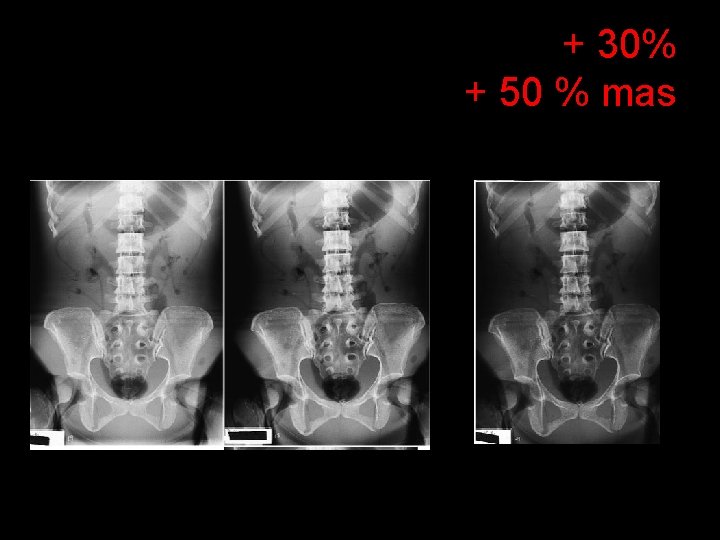

+ 30% + 50 % mas

IMAGES • DENSITY = THE AMOUNT OF BLACKENING “DARKNESS” ON THE RADIOGRAPH - m. As controlled • CONTRAST – THE DIFFERENCES BETWEEN THE BLACKS TO THE WHITES - k. Vp controlled

“Technique” k. Vp , m. As (m. A x s) • m. A- is the current in combination with the time – determines HOW LONG the beam will stay on • Controls the density on the film/image